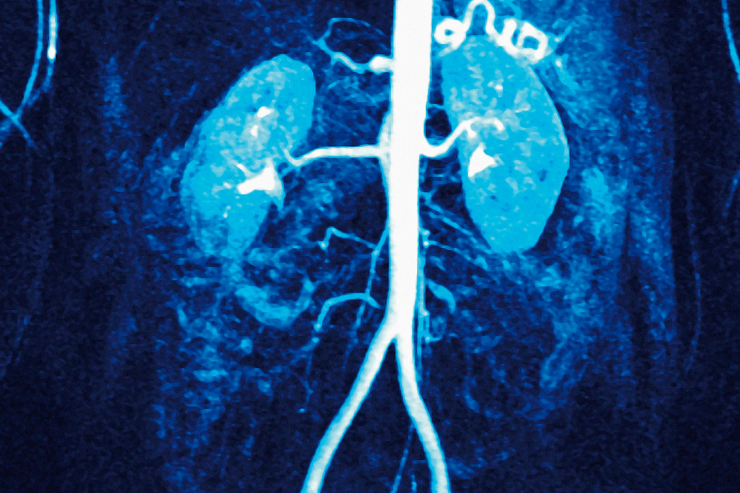

Renal Angiography

Renal Angiography is an imaging procedure that uses contrast dye and X-ray to visualize the blood vessels in the kidneys. It helps diagnose conditions such as renal artery stenosis, aneurysms, and tumors. This procedure is essential for assessing blood flow to the kidneys and guiding appropriate treatment for various renal disorders.

Renal Angioplasty

Renal Angioplasty is a minimally invasive procedure used to treat narrowed or blocked renal arteries. During the procedure, a balloon is inserted and inflated at the site of the blockage to widen the artery, improving blood flow to the kidneys. This technique helps manage conditions like renal artery stenosis and can reduce symptoms and preserve kidney function.